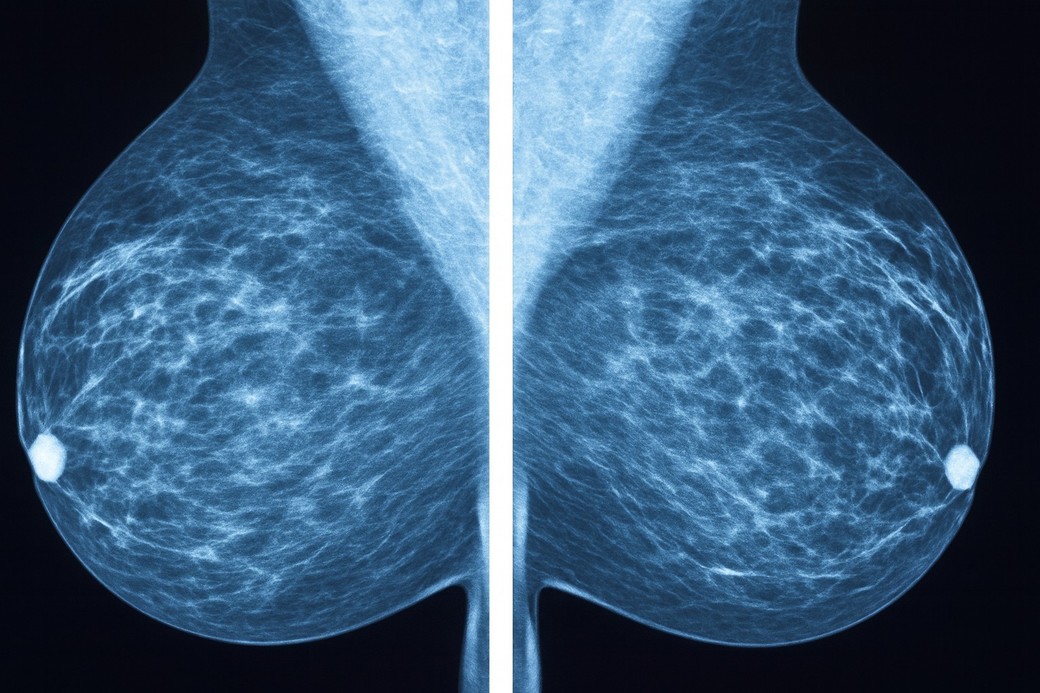

Programul de AI a fost creat pentru a analiza mamografiile realizate de rutină în procesul de diagnostic al cancerului de sân.

Algoritmul a fost „antrenat” în trei etape: în prima fază a analizat zeci de mii de mamografii pentru a recunoaşte structuri de bază precum margini, texturi şi forme; ulterior a învăţat să identifice indicii specifice cancerului, precum delimitarea tumorilor; iar în etapa finală, a integrat informaţii suplimentare despre paciente, cum ar fi vârsta şi tipul tumorii, pentru a estima cu precizie riscul de metastaze.

Rezultatele arată că algoritmul poate clasifica ganglionii ca fiind sănătoşi sau afectaţi de boală cu un nivel ridicat de acurateţe. Potrivit cercetătorilor, biopsia ganglionului santinelă ar fi putut fi evitată în 41,7% din cazuri.